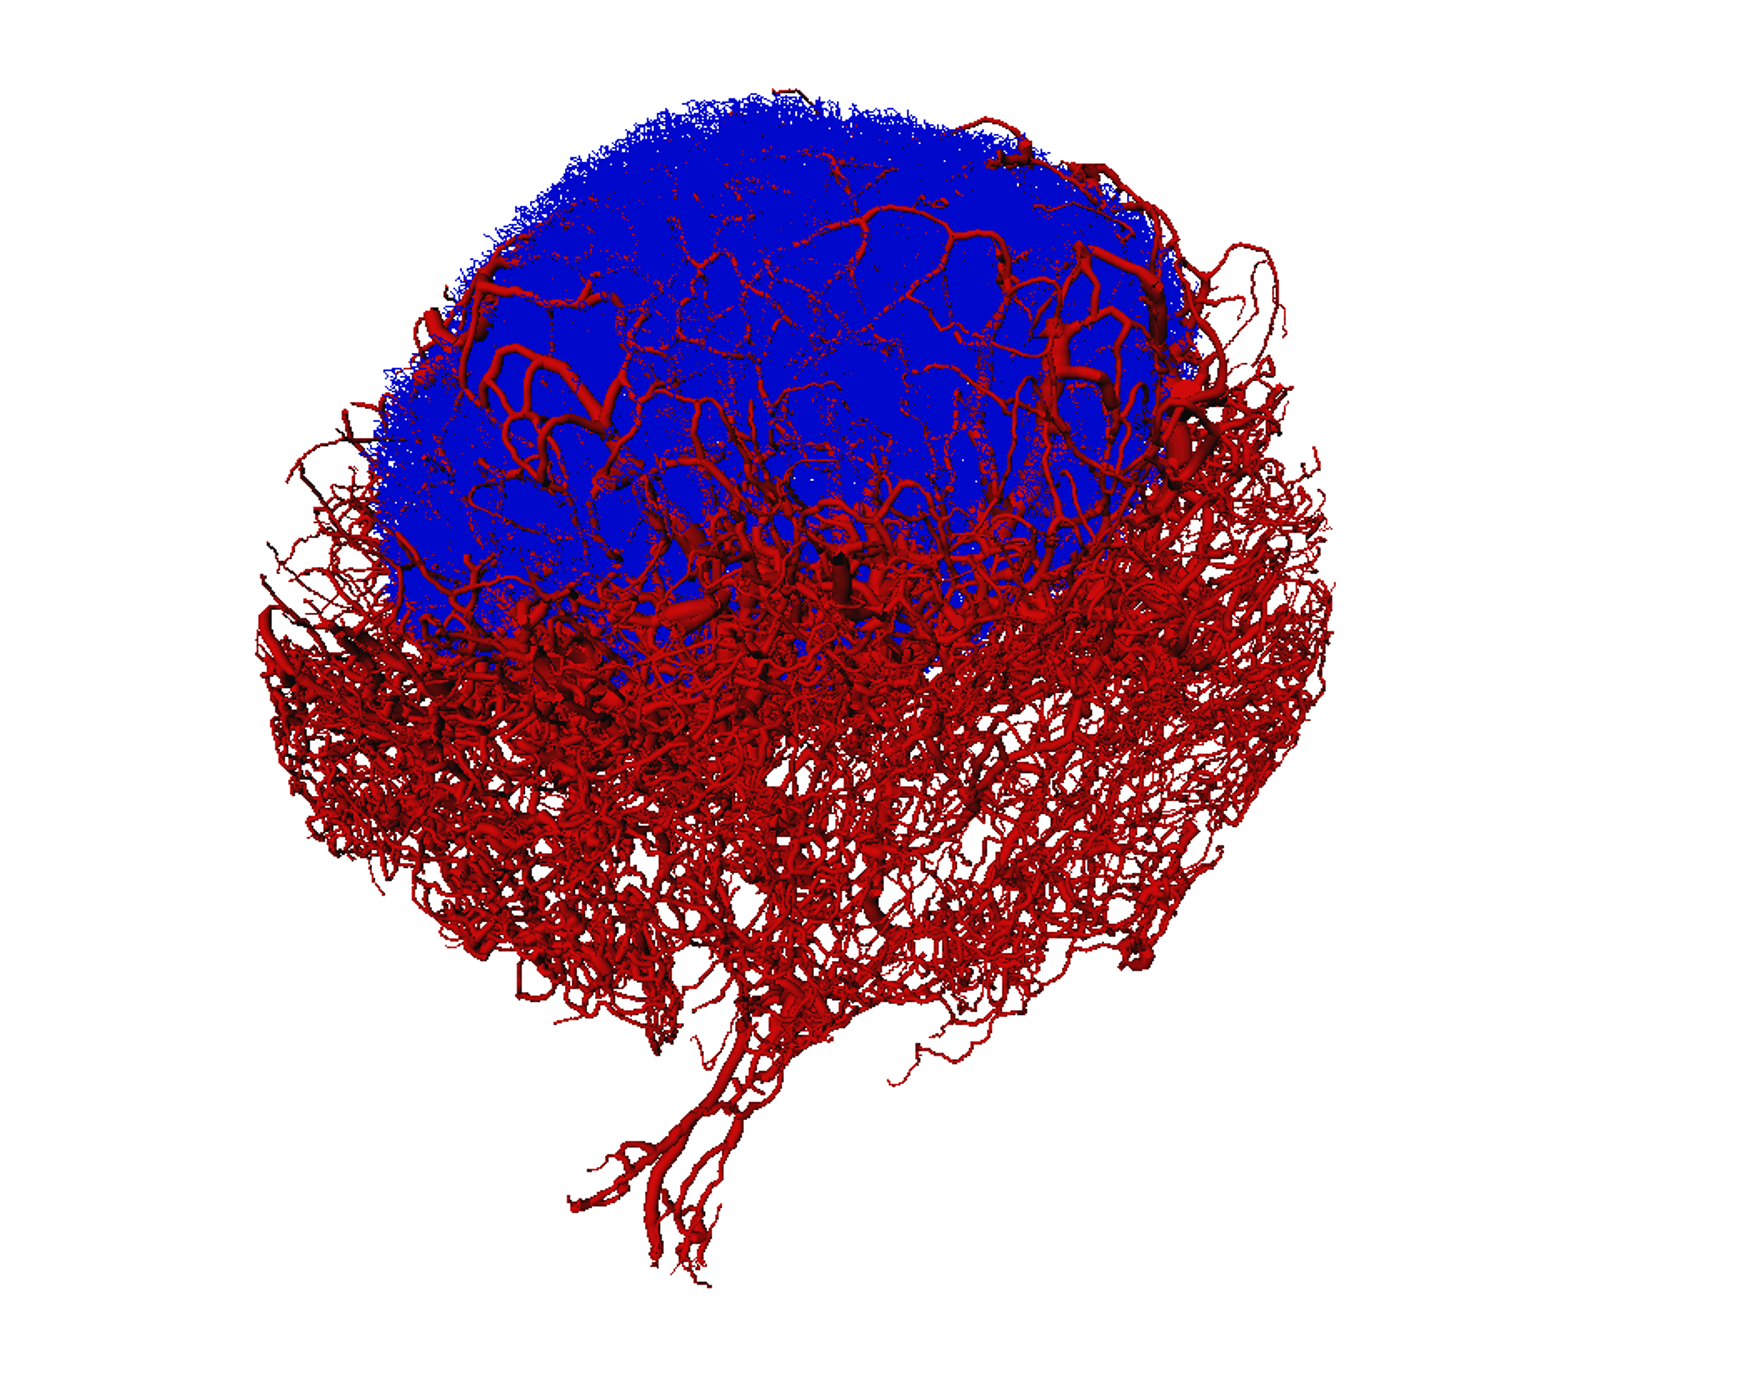

Illuminating tumour micro environments

Advanced technical imaging capabilities and research projects supported by MWC are helping to identify new prognostic and diagnostic biomarkers to advance potential therapeutic tar

New imaging improves our understanding of the immune system

Maurice Wilkins Centre researchers have used novel imaging technology to reveal the structure and inner workings of entire lymph nodes, core components of the body’s immune system.

Mapping microscopic worlds

Maurice Wilkins Centre researchers have used unique microscopic imaging techniques to peer into the three-dimensional structure of blood vessel networks – and new computational tec

Exquisite networks (2011)

Innovative technology developed to study the heart has been adapted for a unique study of the immune system – and will now be applied to cancer, through cross-disciplinary links fo

Lighting up lymph nodes (2009)

Maurice Wilkins Centre researchers have made exciting new discoveries about how human lymph nodes work.